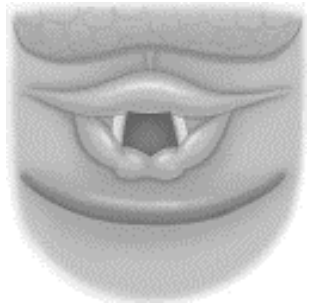

Optou-se, então, por intubação orotraqueal. Realizado

posicionamento correto do doente, pré-oxigenação, indução e

laringoscopia direta com lâmina curva nº 4, com ajuste bimanual

da posição da via aérea. Na melhor posição encontrada,

visualizada via aérea conforme imagem a seguir.

Via aérea com visualização de epiglote, valéculas e parcial da glote,

cordas vocais.

Optou-se, então, por intubação orotraqueal. Realizado

posicionamento correto do doente, pré-oxigenação, indução e

laringoscopia direta com lâmina curva nº 4, com ajuste bimanual

da posição da via aérea. Na melhor posição encontrada,

visualizada via aérea conforme imagem a seguir.

Via aérea com visualização de epiglote, valéculas e parcial da glote,

cordas vocais.